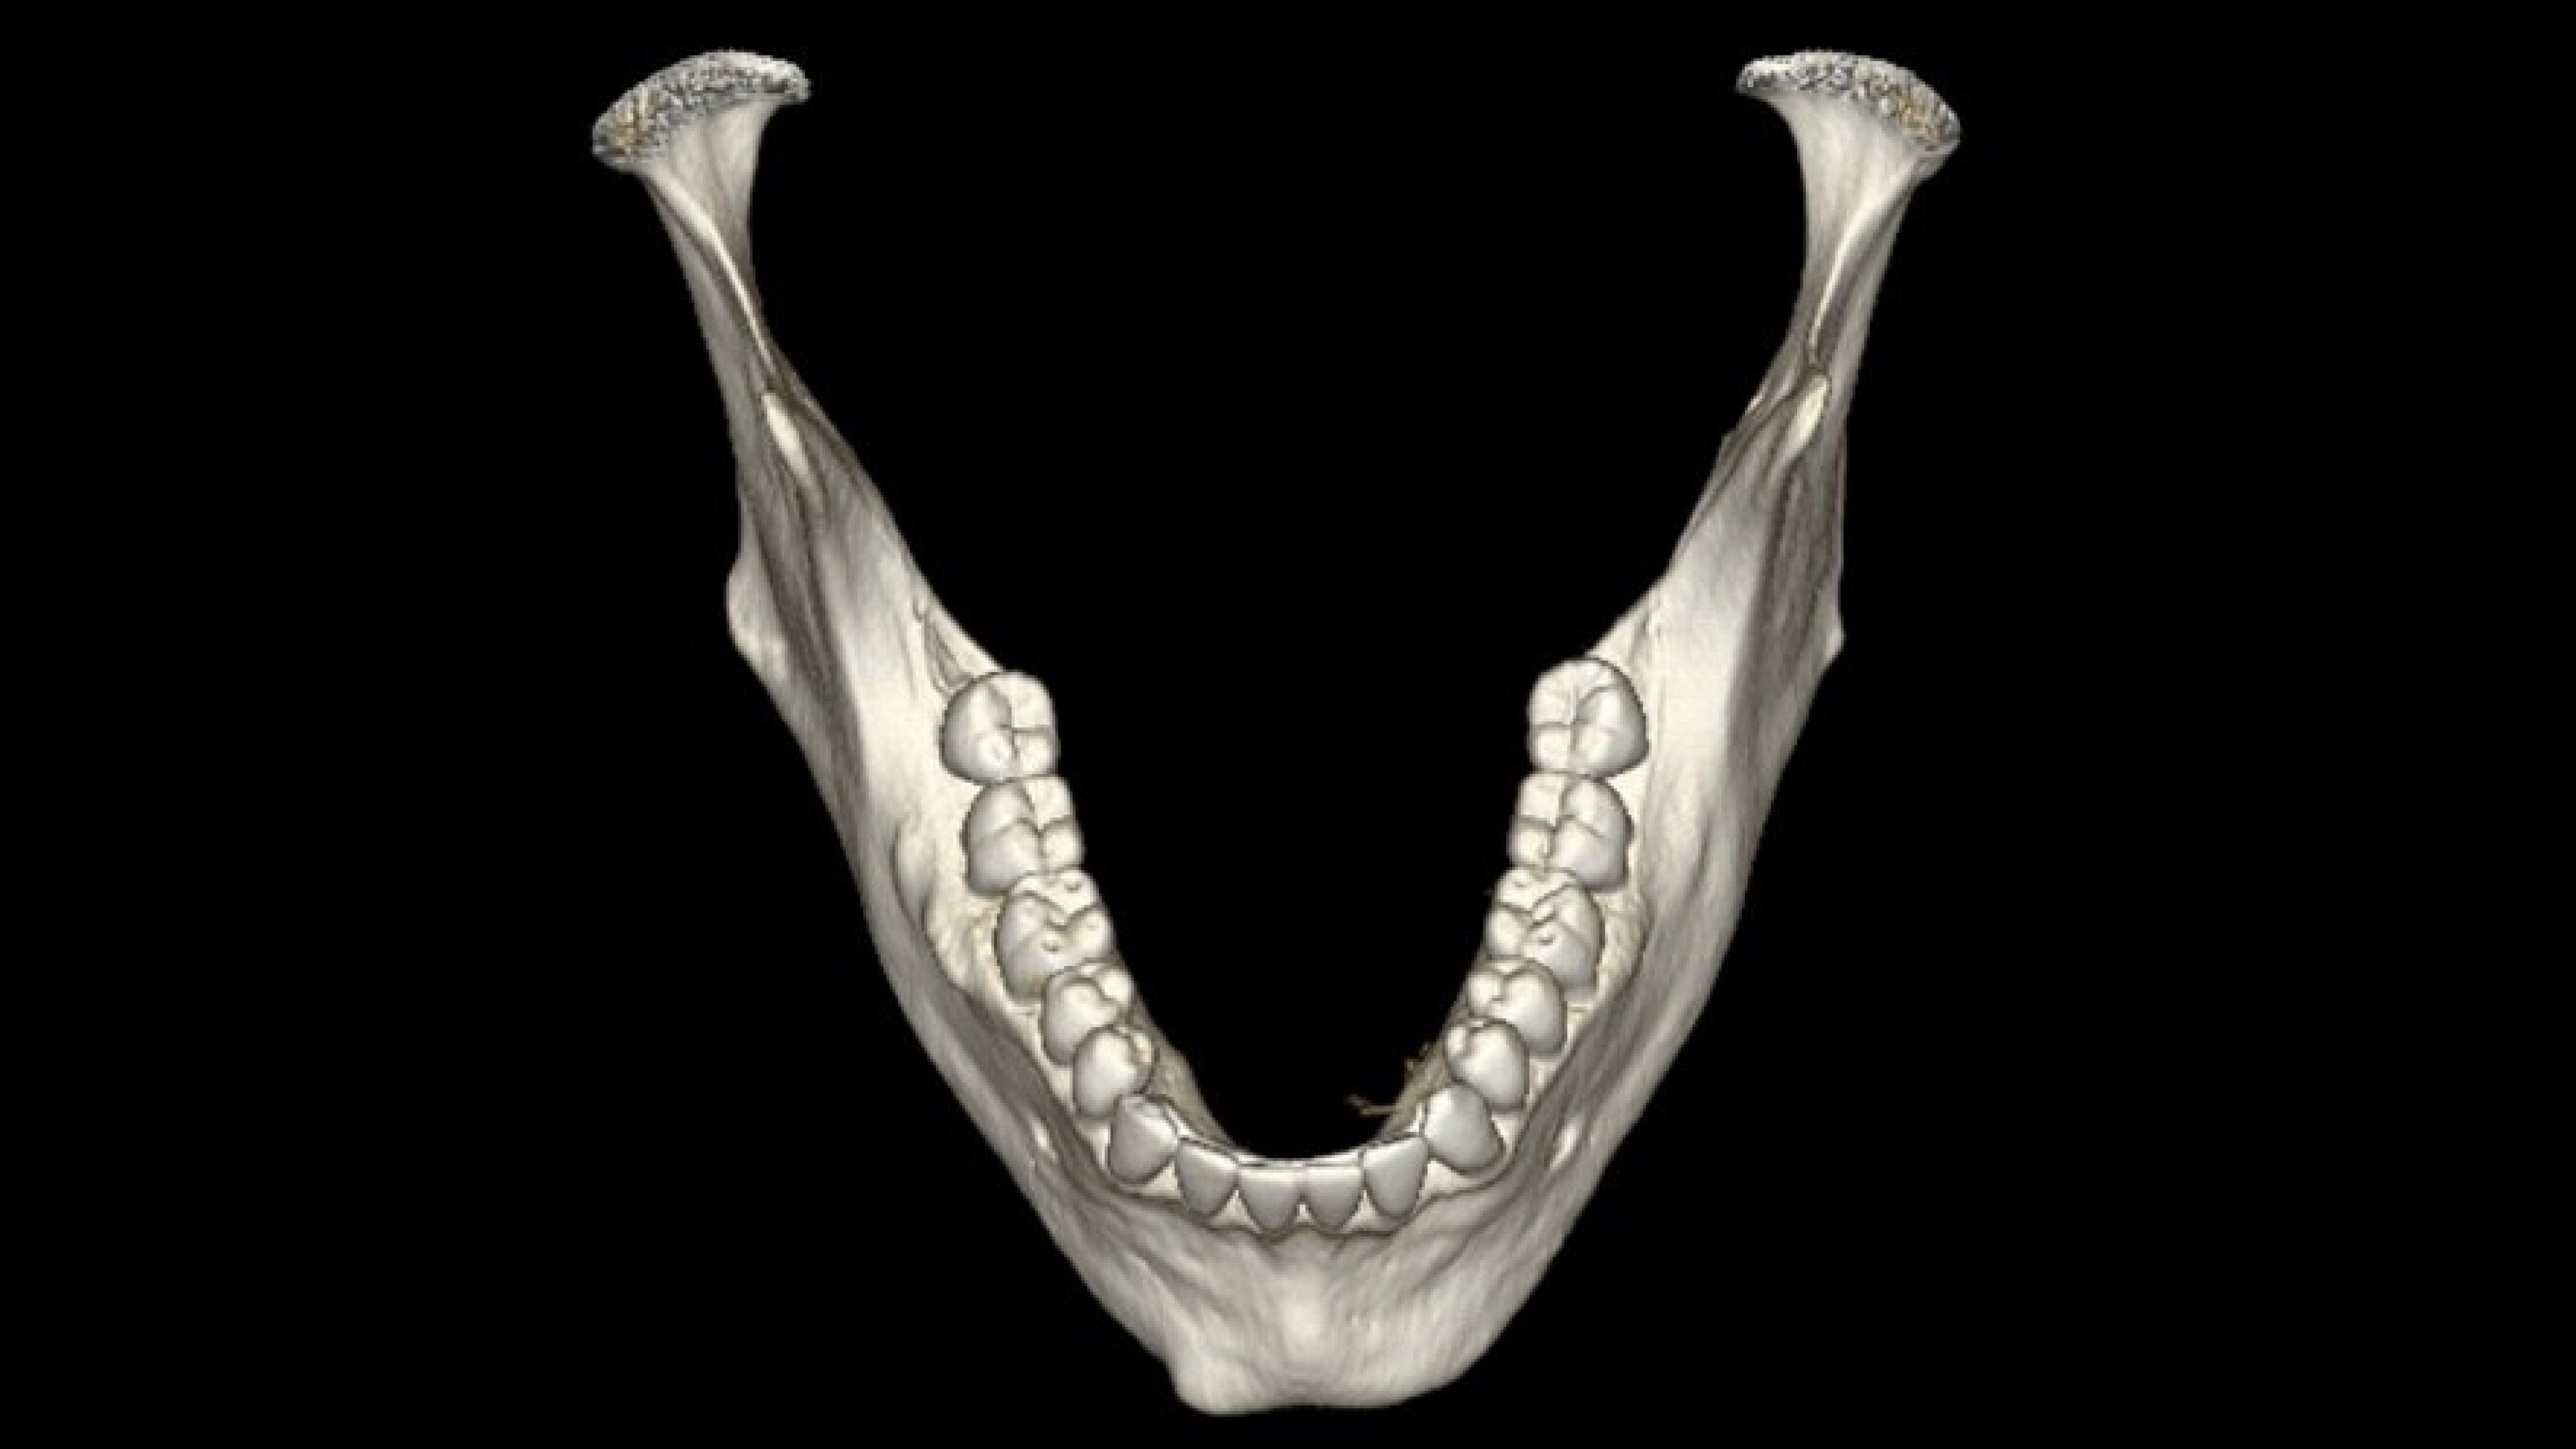

Panorex and oblique views

You can adjust or redraw curves used to generate views during the procedure

• The curve used to generate panorex and oblique views is drawn on selected axial views. It can be adjusted or redrawn easily at any time during Dentascan procedures.

• Axial panorex and oblique views remain cross referenced on the screen. Oblique views are generated in real time when the cursor is moved on axial or panorex views. A similar feature exists when the cursor is moved on a panorex or oblique view.